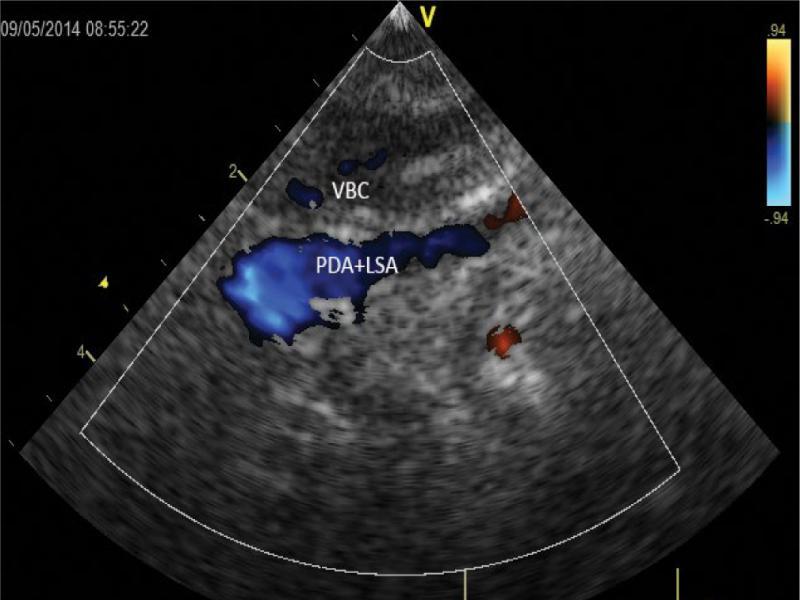

During diastole, the left subclavian artery/ductus arteriosus (PDA+LSA) are more intensely filled, whereas the red color coding for blood flow in the left common carotid artery disappears. Poorly filled with blue color brachiocephalic vein (BCV) is most superficially seen